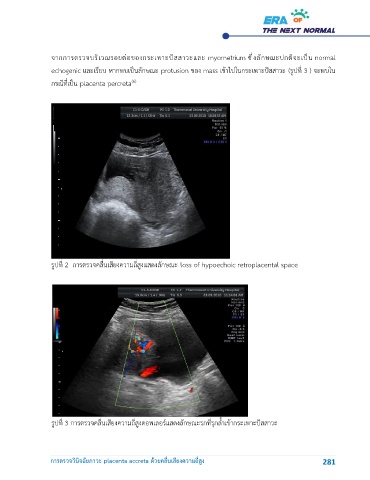

จากการตรวจบริเวณรอยต่อของกระเพาะปัสสาวะและ myometrium ซึ่งลักษณะปกติจะเป็น normal

echogenic และเรียบ หากพบเป็นลักษณะ protusion ของ mass เข้าไปในกระเพาะปัสสาวะ (รูปที่ 3 ) จะพบใน

กรณีที่เป็น placenta percreta

รูปท 2  การตรวจคลื่นเสียงความถี่สูงแสดงลักษณะ loss of hypoechoic retroplacental space

รูปท 3 การตรวจคลื่นเสียงความถี่สูงดอพเลอร์แสดงลักษณะรกที่รุกล้ำเข้ากระเพาะปัสสาวะ